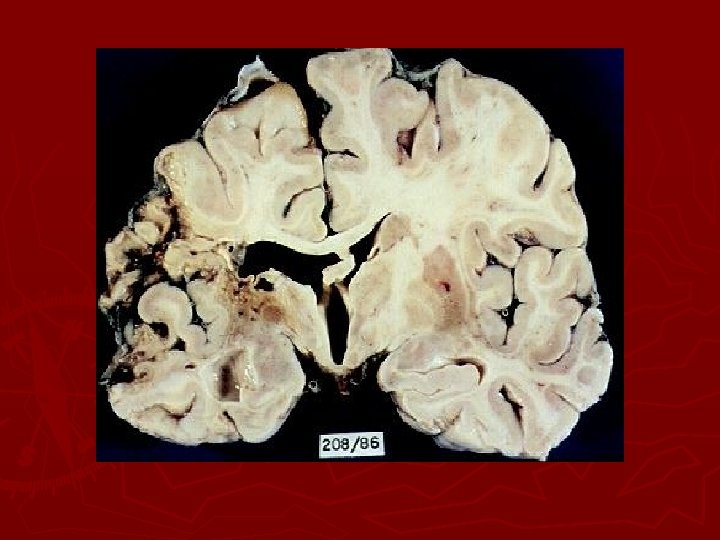

Hemorrhagic stroke ► Intracerebral hemorrhage is bleeding within the brain caused by rupture of a blood vessel that lasts from minutes to days. ► Most commonly caused by HTN ► May be caused by brain tumors, trauma, thrombolytic drugs, and ruptured aneurysms.

Hemorrhagic stroke ► Blood within the closed area of the brain imposes pressure on the brain tissue and displaces brain tissue and decreases blood flow to brain. ► Clinical manifestations depends on the site and amount of hemorrhage and resultant damage. ► Poor prognosis; 70% die